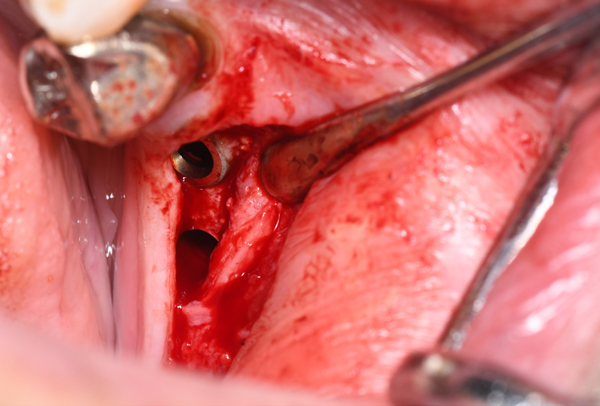

症例6. 再生療法-EPPT-

![]() |

| 右上2番 | 遠心の垂直性骨欠損 |

| EPPT(Entire Papilla Preservation Technique) 歯冠乳頭を保存し、 治癒と審美的な予後を 期待できる術式 |

人工骨の填入 |

|

| 縫合 |